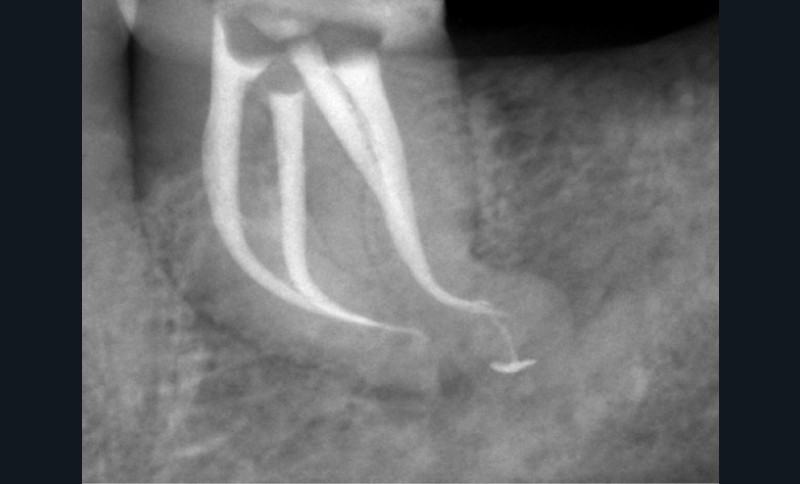

Endal, en 2011, montrait également, en utilisant le micro CT Scanner, l’insuffisance de nettoyage des isthmes inter-canalaires à nos techniques conventionnelles [19]. L’utilisation du laser Er:YAG devenait alors incontournable dans le nettoyage de ces isthmes et des zones non instrumentées (fig. 2 et 3).

Cette pénétration s’étend de la chambre pulpaire au réseau canalaire, isthmes, deltas apicaux et tubulis dentinaires. Il a été démontré que l’effet de cavitation pourrait permettre la destruction des bactéries à des profondeurs de 300 à 400 µm au sein des surfaces irradiées [20].

Si l’étude de Peters [18] nous montre que l’instrumentation laisse 35 % du volume canalaire non instrumenté, Ricucci et Siqueira montrent que la préparation physico-chimique n’élimine que partiellement les tissus nécrotiques à l’entrée des canaux latéraux, des isthmes et des ramifications apicales, en laissant des tissus enflammés et infectés, en association avec des lésions apicales [29] (fig. 4 et 5).